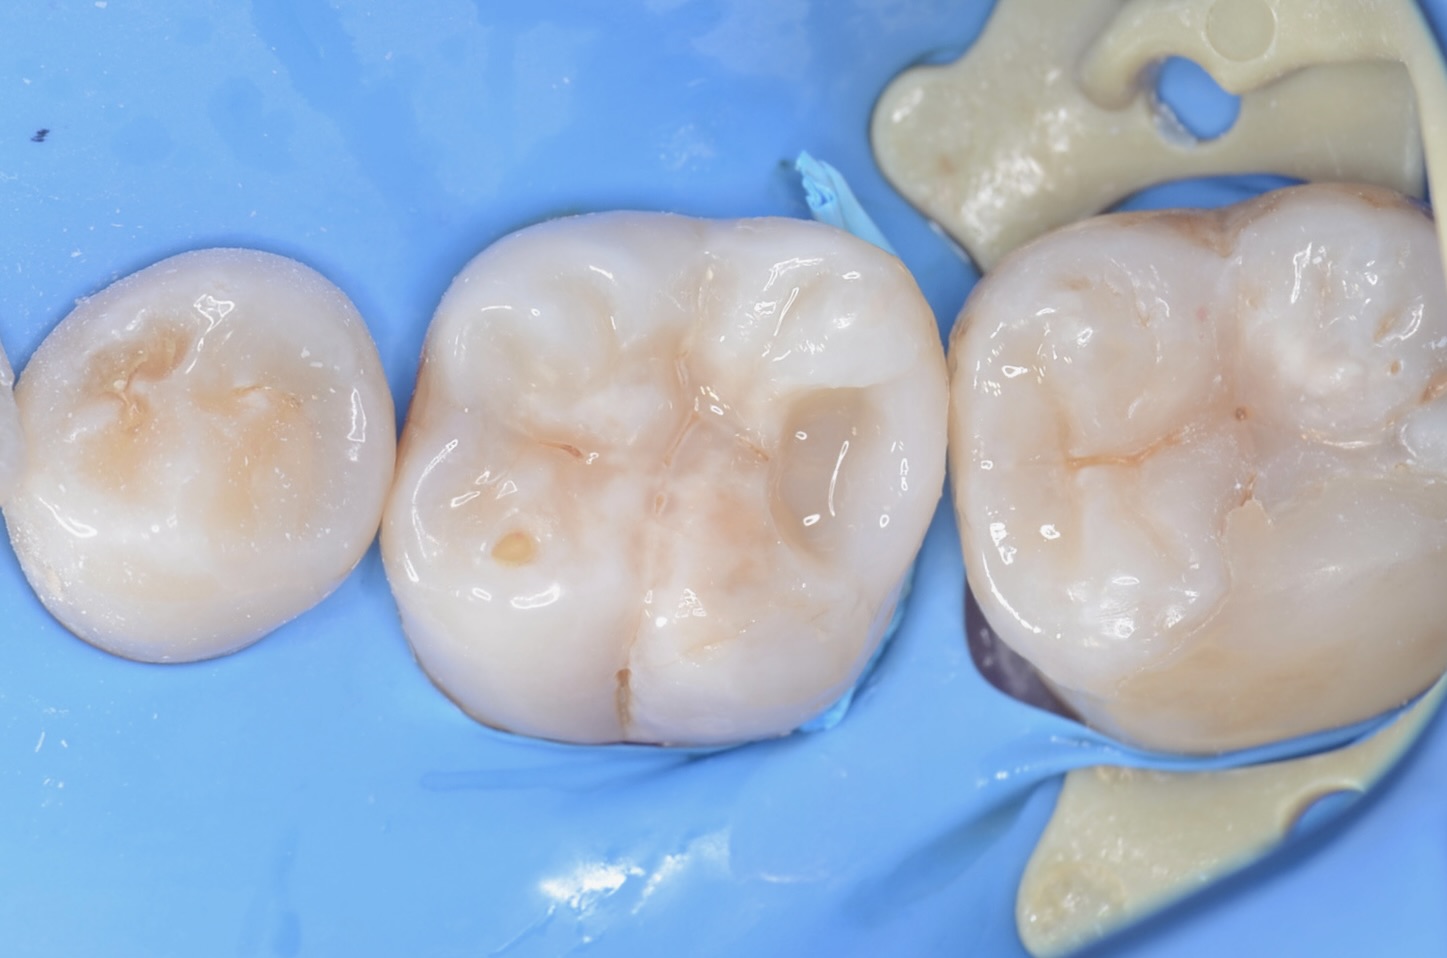

3Dプリンターテクニック

フロワブルレジンを用いて、その表面張力を利用して滑らかで段差のないレジン充填を実現させます。 セパレーターで歯間離開させながら光を当てながらレジンを硬化させる3Dプリンターテクニックを用いて治療しました。 -

ダイレクトボンディング終了

咬合面にはペースト状のレジンで、形態を作りました。天然歯の自然な形態を模倣してレジンを充填しました。 -